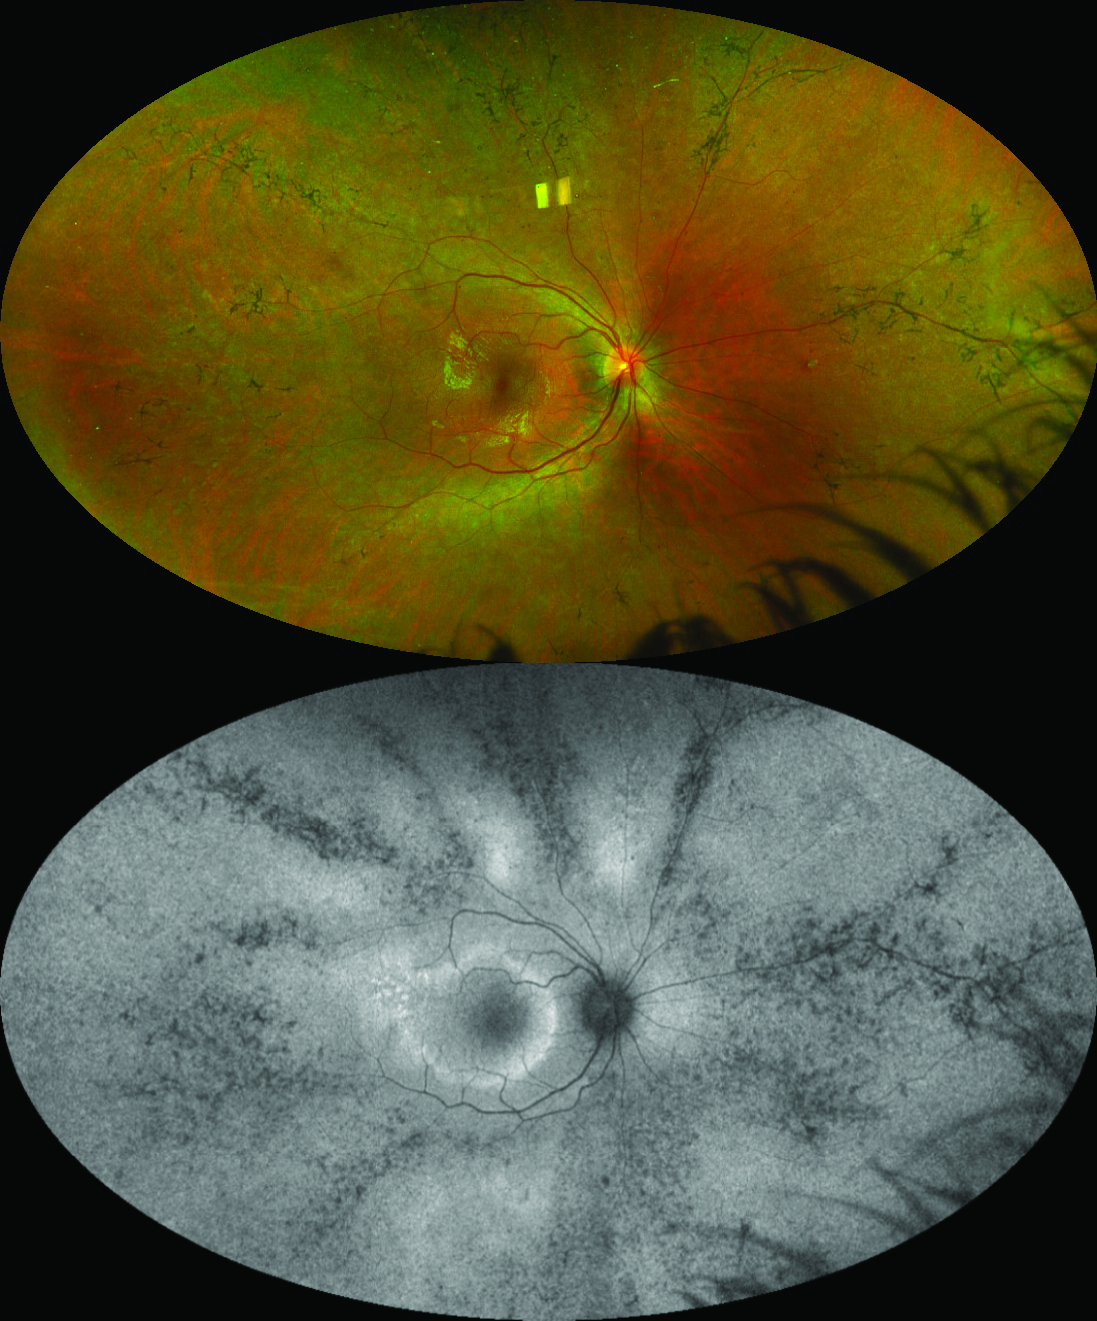

Request pdf | sensitivity and specificity of the optos optomap for detecting peripheral retinal lesions | to compare the sensitivity and . The integration of uwf guided swept source oct with optomap gives eye care professionals unprecedented capability to manage retinal disease," . Interference may occur in the vicinity of equipment marked with this symbol. Tona) to be integrated as the new standard in optometric screening in germany. G102748/5gwe page 11 of 37 english . All information contained in this document is confidential and solely the . Technicians can effectively image patients because the device guides you through . Optos optomap und zeiss clarus.

The integration of uwf guided swept source oct with optomap gives eye care professionals unprecedented capability to manage retinal disease," . To open this utility and view instructions on how to use it, . Request pdf | sensitivity and specificity of the optos optomap for detecting peripheral retinal lesions | to compare the sensitivity and . Tona) to be integrated as the new standard in optometric screening in germany. Documentation of retinal pathology with an initial optomap also supports.

Documentation of retinal pathology with an initial optomap also supports. P200 Brochure Optos